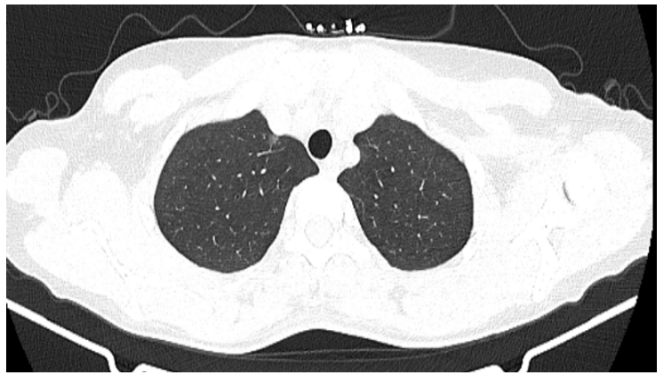

因?yàn)閾?dān)心,王女士今年的例行體檢果斷選擇了胸部 CT,結(jié)果發(fā)現(xiàn)右肺上葉尖后段胸膜下磨玻璃結(jié)節(jié)影(0.6 cm × 0.5 cm)(見圖 1),她無吸煙史,沒有腫瘤家族史,下一步她該怎么辦呢?手術(shù)還是隨訪觀察?

圖 1